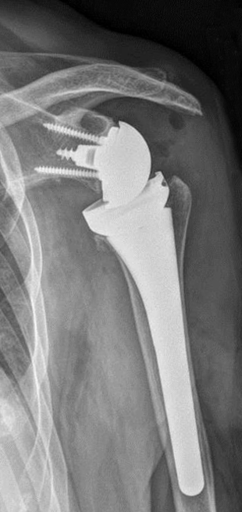

On the glenoid side, the surgeon can choose from three baseplate sizes, to fit their patient’s glenoid anatomy. There is no concern of over or under sizing and the three options allow the surgeon to also accomplish maximum screw fixations with the three locking screw design (4.5 mm locking screws superior and inferior and a 6.5 mm central locking screw). This is the only system available that offers three glenosphere diameters (36 mm, 39 mm, 42 mm). For each size there are three glenosphere options (central, lateralized and offset). Although at “face value” all these options may be “dizzying,” it is in fact this variety that gives the orthopaedic shoulder surgeon the ability to address the expanded indications for a reverse shoulder patient head on, and removes the need to fit a “square peg into a round hole.”

On the humeral side, the two available neck angles (135 degree and 155 degree) once again give the surgeon options that are not available in other systems. The clinical concern of scapular notching is becoming more evident with our critical evaluation of patients treated early on with the reverse shoulder and the 135-degree neck angle has definitely shown to decrease the incidence of scapular notching. In fact, it was during one of the first revision cases that the surgeon was unable to reduce the 155-degree humeral trial and by simply adjusting the humeral implant angle of the trial to 135 degrees, reduction was easily accomplished. This eliminated the need for the surgeon to have to use a smaller diameter glenosphere and risk exposing their patient to an increased risk of instability.

It is well recognized that the amount of offset seen in the proximal humerus has a wide range from anterior to posterior. The Arthrex Univers Revers has a unique ability to address humeral offset, allowing the component to sit centrally in the patient’s humeral metaphysis, which allows forces across the glenohumeral joint to be evenly distributed. Finally, the “trapezoidal” design of the metaphyseal portion of the humeral component gives it the ultimate press-fit fixation within the proximal humerus, avoiding the need for cement in the majority of cases.